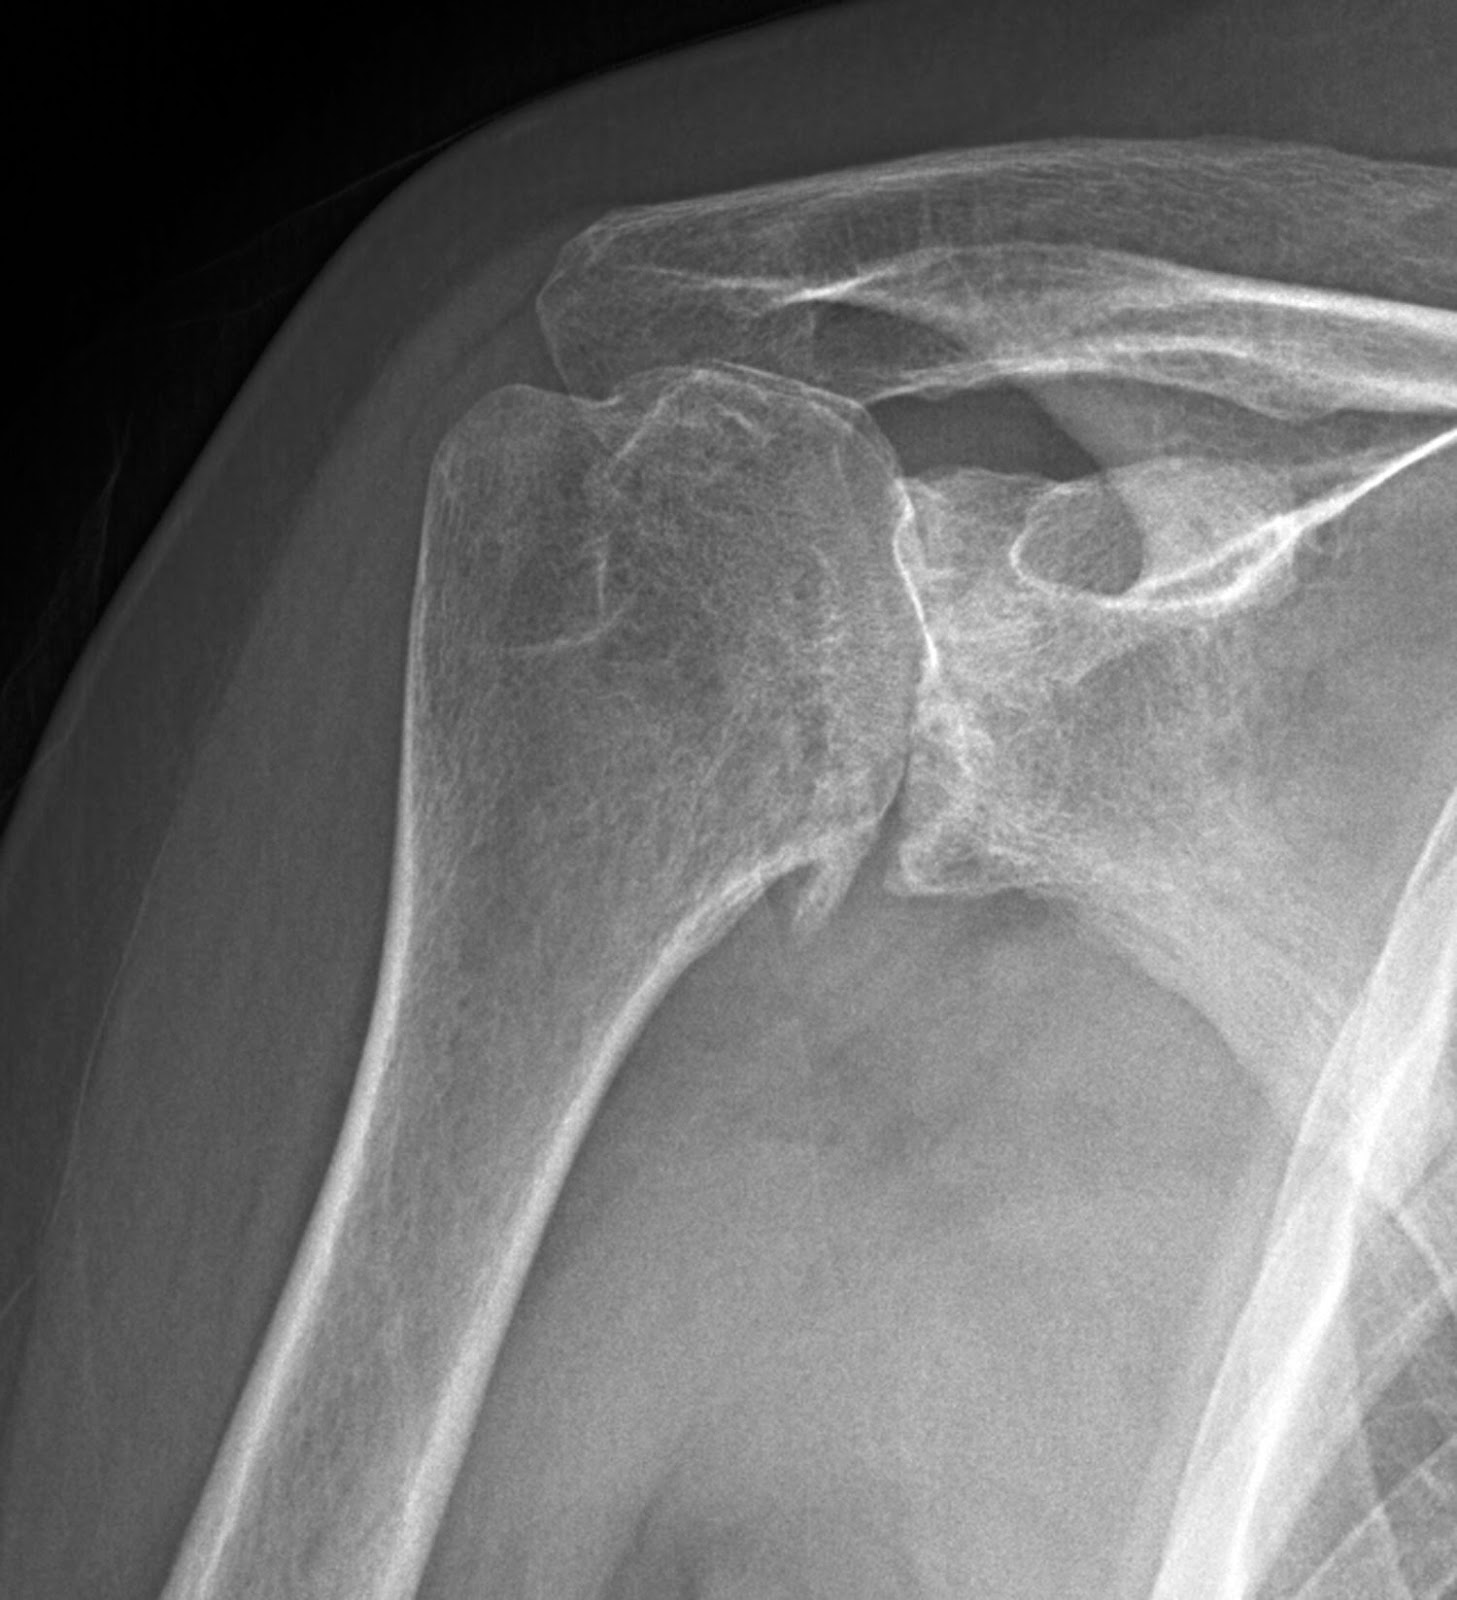

SHOULDER ARTHRITIS Arthritis In Shoulder Muscles Read on to learn how an. learn about the types of shoulder arthritis, including osteoarthritis and rotator cuff tear arthropathy, and the associated surgical and nonsurgical treatments. there are five types of arthritis that can affect your shoulder, including rheumatoid arthritis and. There are many nonoperative treatments. here is information about the causes of and treatments for. Arthritis In Shoulder Muscles.

Shoulder Osteoarthritis Diagnosis Arthritis In Shoulder Muscles There are many nonoperative treatments. In an arthritic shoulder, inflammation causes pain and stiffness. learn about the types of shoulder arthritis, including osteoarthritis and rotator cuff tear arthropathy, and the associated surgical and nonsurgical treatments. simply defined, arthritis is inflammation of a joint. here is information about the causes of and treatments for shoulder osteoarthritis. In an. Arthritis In Shoulder Muscles.